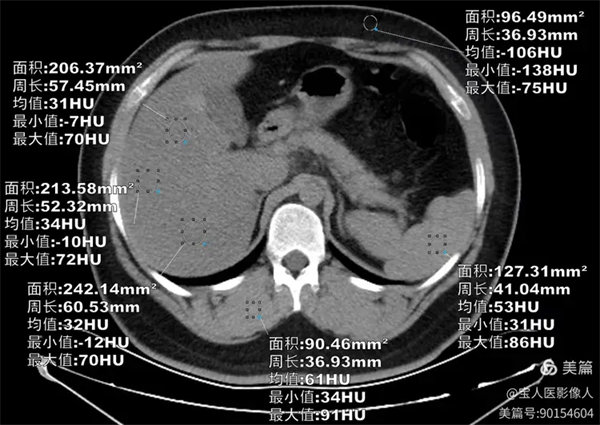

图1

CT轴位,肝形态,大小正常,CT值最低约31HU,较正常肝实质密度降低。